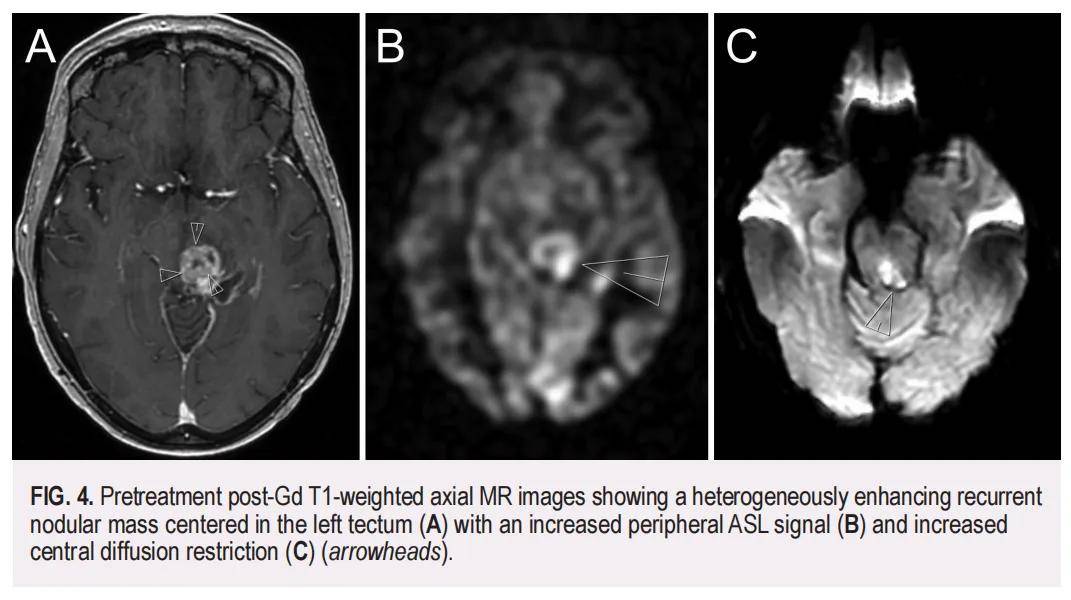

术后病理学检查证实为中分化鳞状细胞癌(SCC),其PD-L1综合阳性评分(CPS)<1%。此外,对切除的顶盖病变进行的NGS panel检测显示,SCC与原始表皮样囊肿(EC)存在相同变异,包括TP53(F113V,可能致病性)、CASP8[I315V,意义未明变异(VUS)]和MCL1(T38S,VUS)。进一步分析显示,该SCC的肿瘤突变负荷(TMB)为 14.9 muts/Mb。两个样本间的相同变异强烈提示两者存在共享的突变特征,并支持EC作为前体病变,其中致病性TP53突变促进了肿瘤发生。值得注意的是,SCC中还存在一个额外的PTEN变异(D92H,可能致病性),提示这是一个促成疾病进展的第二个驱动突变。在SCC样本中,TP53和PTEN突变的变异丰度(VAFs)分别高达 81% 和 79%。整体而言,这有力支持了初始EC的恶性转化。术后 2 个月的MRI显示,残留肿瘤主要位于切除腔下缘(图3A和B)。患者随后接受了容积调强弧形治疗(VMAT),针对原始EC、切除腔边缘及顶盖次全切除的强化区域,处方剂量为 54 Gy(分 30 次照射)。VMAT治疗后 5 个月的随访MRI显示治疗反应良好,顶盖病变体积缩小(图3C和D)。然而,VMAT治疗 1 年后,患者出现复视加重,并伴有右手和右脚麻木。此时MRI显示左侧顶盖不均质强化肿块出现间隔期增大(大小为 2.6×1.9×2.6 cm),并观察到中心扩散受限及动脉自旋标记(ASL)信号增强,提示肿瘤复发(图4)。后续PET/MRI显示该病灶有显著氟代脱氧葡萄糖摄取。

▲图4 治疗前Gd T1加权轴向 MR 图像显示左顶盖中心存在不均匀增强的复发性结节性肿块(A),外周ASL信号增强(B),中央扩散限制增强(C)(箭头)